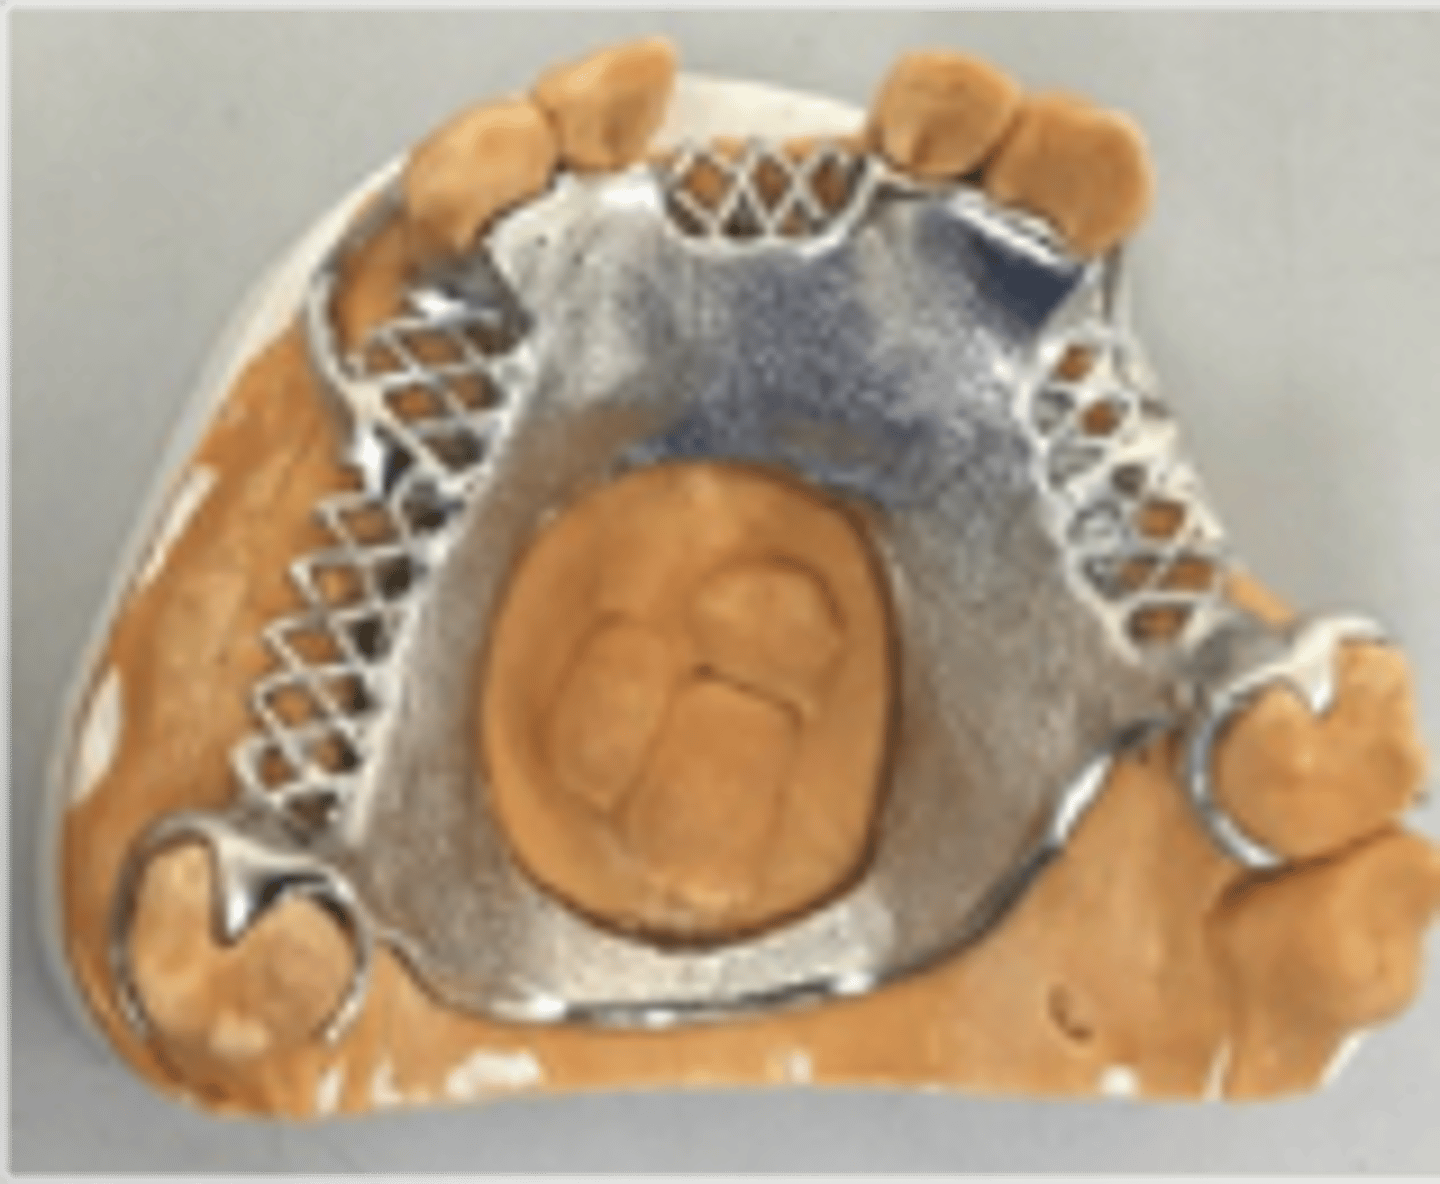

Acrylic Retention area

Since acrylic and metal do not bond, mechanical retention is required: Lattice, mesh, post, loop, beading

relief

mesh and lattice are made with ______ underneath to allow acrylic to wrap around metal completely

Beading and loops

hold denture tooth "veneer" (occluding surface is part of metal framework)

Tissue stop

small projection of metal at the distal end of an extension base framework that contacts the cast and prevents downward movement of the acrylic retention area during the processing of the RPD for delivery